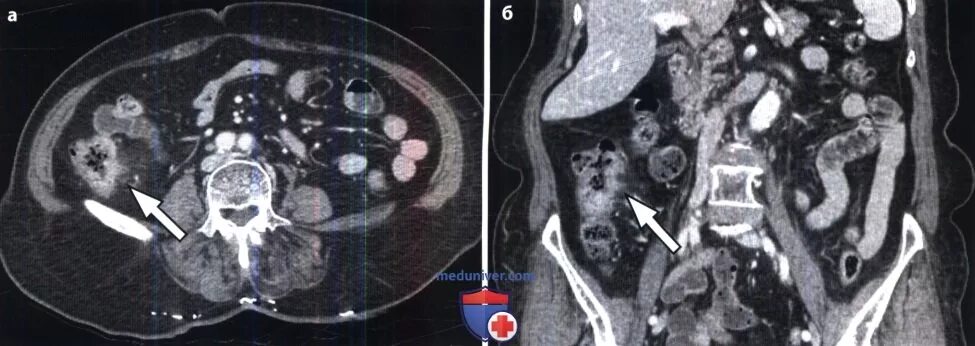

Метастазы при раке сигмовидной кишки